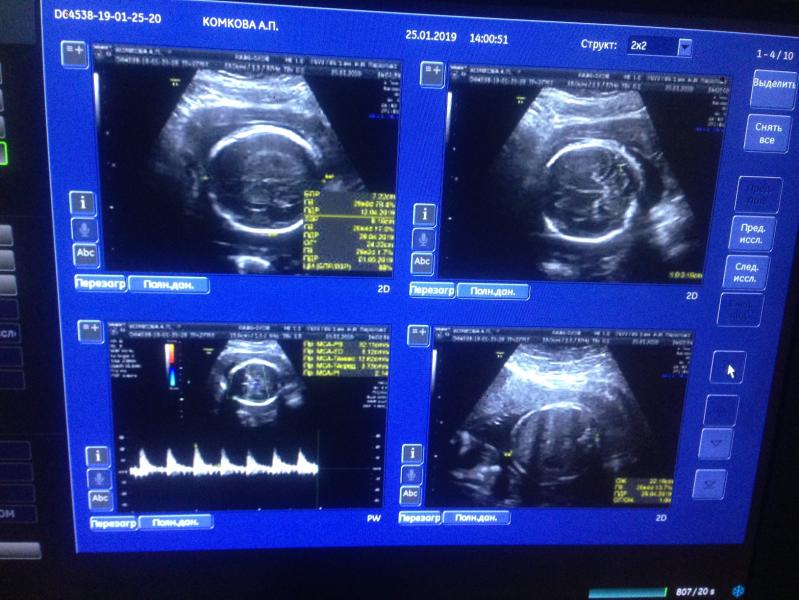

Сходила сегодня на узи ❤️👶🏻 господи как он быстро растёт 🤰🏻

Весим уже 1008 грамм 👶🏻

Проблем никаких нет . Узи показывает что мое солнце полностью хорошо чувствует себя . Сердцебиение 143 уд/мин

25.01.2019